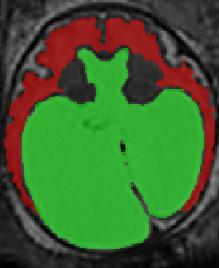

Limiting failures of machine learning systems is of paramount importance for safety-critical applications. In order to improve the robustness of machine learning systems, Distributionally Robust Optimization (DRO) has been proposed as a generalization of Empirical Risk Minimization (ERM). However, its use in deep learning has been severely restricted due to the relative inefficiency of the optimizers available for DRO in comparison to the wide-spread variants of Stochastic Gradient Descent (SGD) optimizers for ERM. We propose SGD with hardness weighted sampling, a principled and efficient optimization method for DRO in machine learning that is particularly suited in the context of deep learning. Similar to a hard example mining strategy in practice, the proposed algorithm is straightforward to implement and computationally as efficient as SGD-based optimizers used for deep learning, requiring minimal overhead computation. In contrast to typical ad hoc hard mining approaches, we prove the convergence of our DRO algorithm for over-parameterized deep learning networks with ReLU activation and a finite number of layers and parameters. Our experiments on fetal brain 3D MRI segmentation and brain tumor segmentation in MRI demonstrate the feasibility and the usefulness of our approach. Using our hardness weighted sampling for training a state-of-the-art deep learning pipeline leads to improved robustness to anatomical variabilities in automatic fetal brain 3D MRI segmentation using deep learning and to improved robustness to the image protocol variations in brain tumor segmentation. Our code is available at https://github.com/LucasFidon/HardnessWeightedSampler.